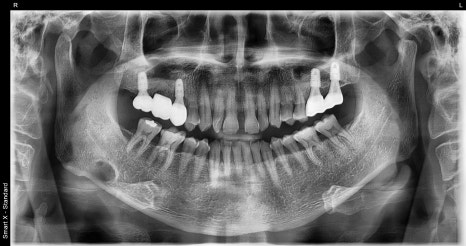

왼쪽 사진: 환자분 첫 내원 당시 파노라마 엑스레이 사진입니다.

오른쪽 사: 초기 구강 내 사진으로, 어금니 쪽 잇몸과 치아 상태를 보여줍니다.

맨 뒤 큰 어금니는 처음 내원 시부터 결손된 상태였고, 그 앞 어금니는 치근단 염증이 심한 상태였습니다.

또한 작은 어금니는 흔들림이 심해, 두 치아 모두 발치 후 임플란트로 대체하였고, 전체 잇몸 치료도 함께 병행하여 치료 계획을 수립했습니다.